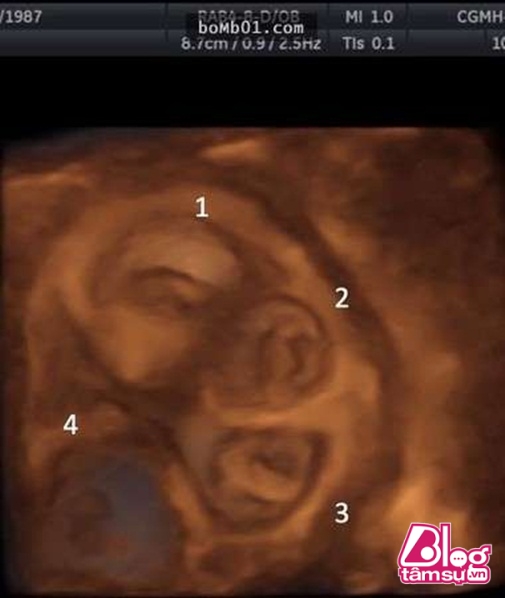

Tuy nhiên, sau 1 thời gian sử dụng thuốc, cô gái liên tục bị những cơn đau bụng hành hạ, cô đã đến gặp bác sĩ để kiểm tra ngã ngửa khi nhìn thấy những hình ảnh siêu âm. Theo các bác sĩ, trong cơ thể cô gái có tim thai đang đập và nó đang gây nguy hiểm đến tính mạng của cô gái.

Các bác sĩ cho rằng, cô gái trẻ đã mang thai ngoài tử cung và đây còn là song thai. Đây là 1 trường hợp rất hiếm, nó có thể gây nguy hiểm cho cả mẹ và 2 đứa trẻ nhưng cô gái và gia đình vẫn quyết định giữ lại song thai này.